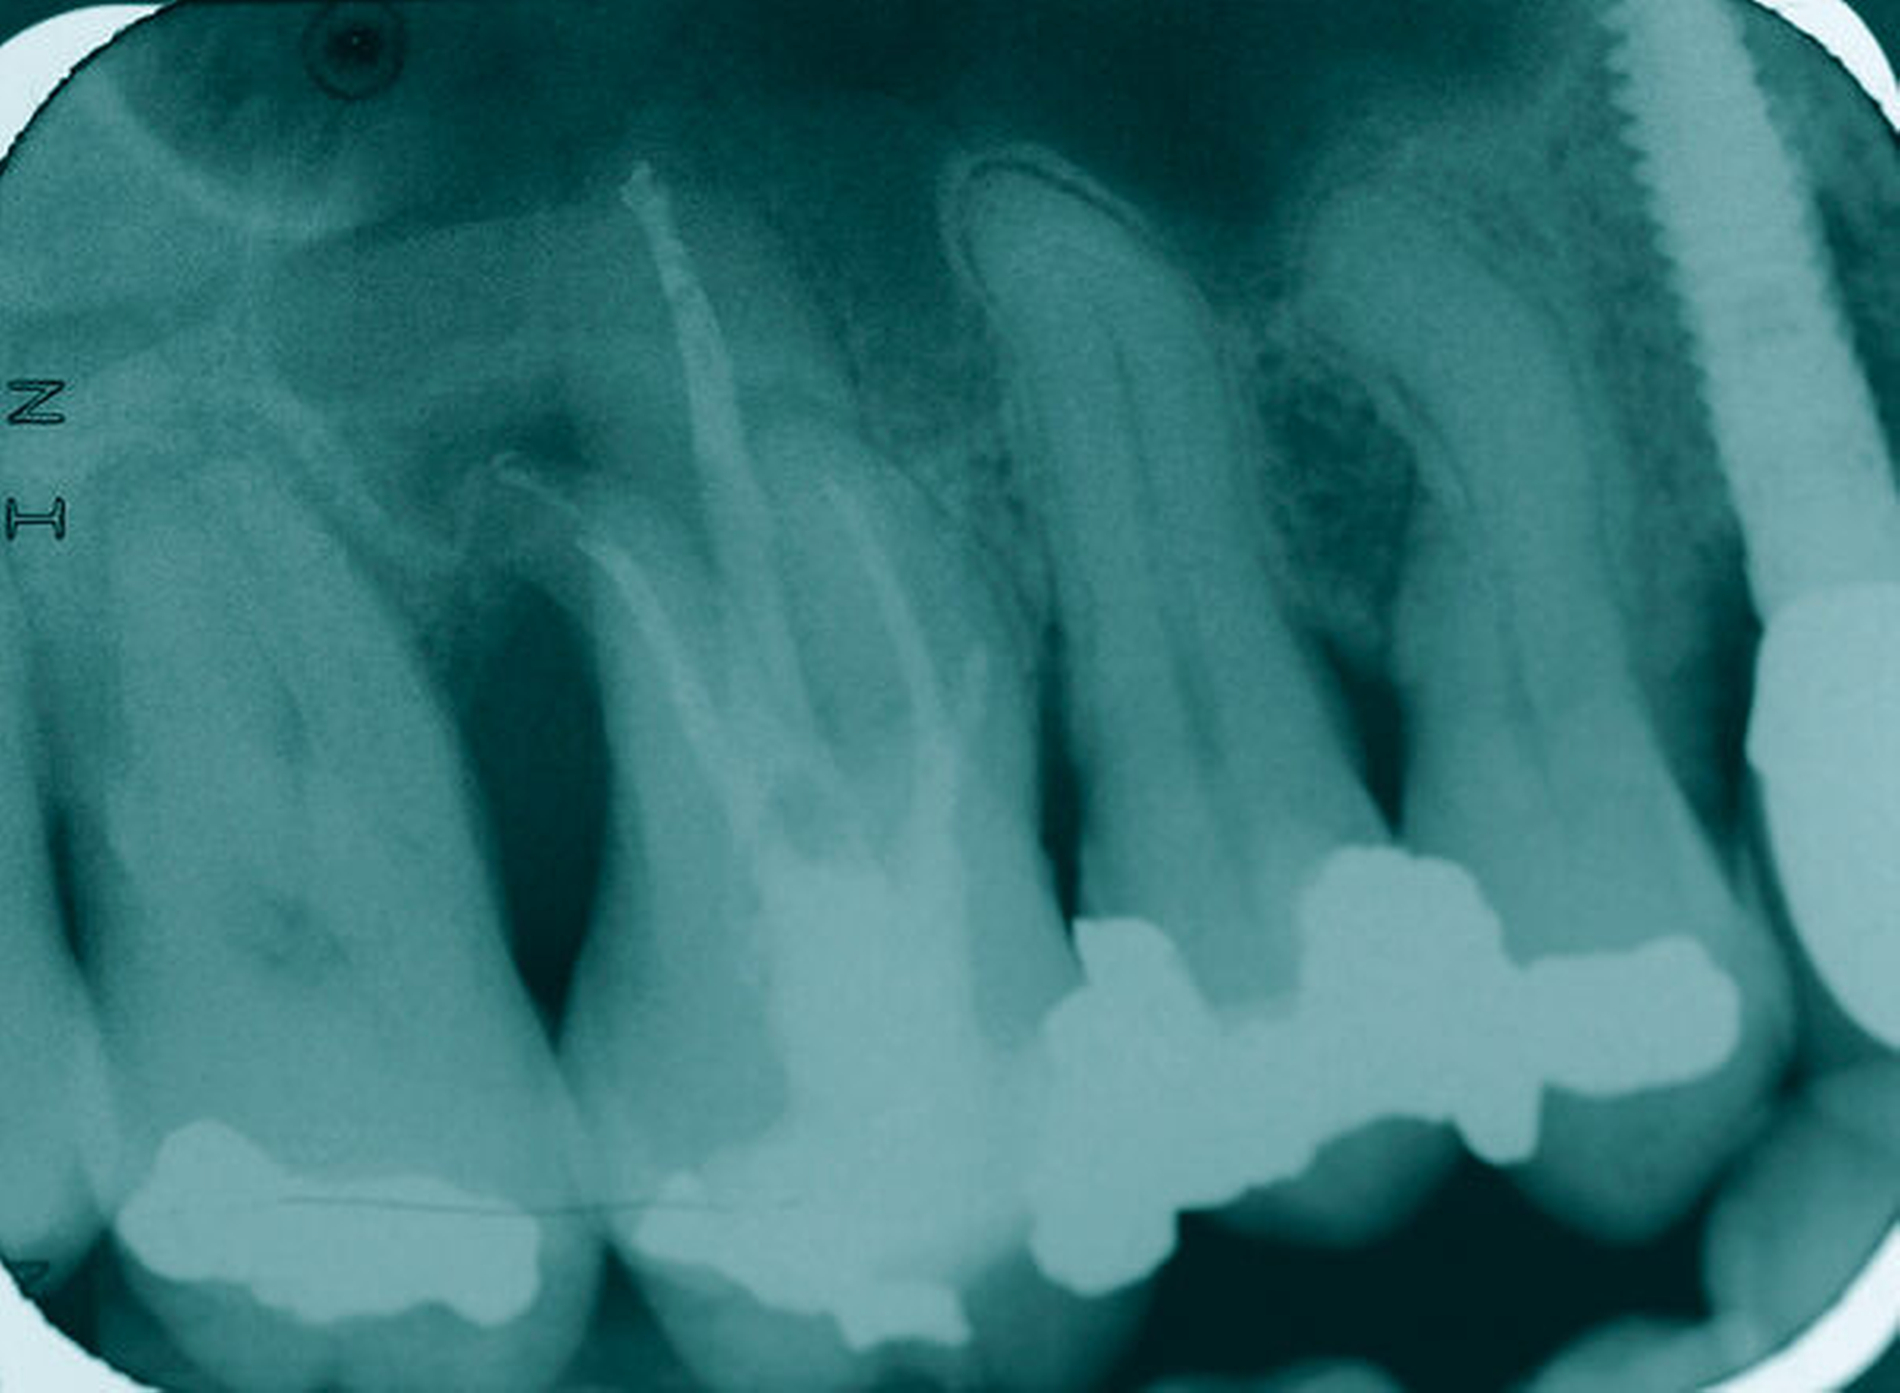

Ein 59-jähriger Patient stellte sich erstmals 2015 mit rezidivierenden pochenden Beschwerden und zeitweise zusätzlich auftretendem Pusaustritt an Zahn 16 vor. Klinisch zeigte sich ein ausgeprägter Attachmentverlust distal mit bis apikal sondierbarer distobukkaler Wurzel, Furkationsbeteiligung und Pusaustritt sowohl über den Parodontalspalt als auch durch einen distobukkal gelegenen Fistelausgang. Zunächst erfolgte die endodontische Behandlung des Zahnes 16 mit anschließender systematischer PA-Therapie. Bei persistierender parodontaler Problematik an 16 wurde die Möglichkeit der Teilamputation der distobukkalen Wurzel mit dem Patienten diskutiert, um die Hygienefähigkeit und damit die Prognose des Zahnes zu verbessern. Auch über die Extraktion als Alternative wurde der Patient aufgeklärt. Er war allerdings motiviert, seinen Zahn so lange wie möglich zu erhalten.

So erfolgte die Amputation der distobukkalen Wurzel mit anschließender Versorgung des Zahnes mittels Vollkrone. Die Situation an 16 ist seitdem für den Patienten subjektiv stabil, die aktuelle Röntgenkontrolle zeigt jedoch eine Progredienz der parodontalen Defekte trotz regelmäßiger UPT und subjektiv guter Mitarbeit des Patienten, was die Prognose des Zahnes negativ beeinflusst. Ursächlich hierfür kann eine persistierende parodontale Infektion durch den trotz Wurzelamputation immer noch schwer für die häusliche Mundhygiene zugänglichen Furkationsbereich mit enger Lagebeziehung der mesiobukkalen und der palatinalen Wurzel sein. Der Patient ist allerdings aktuell mit der Situation zufrieden und beschwerdefrei und wünscht daher noch keine Extraktion des Zahnes, auch wenn diese sich nun fünf Jahre nach dem initialen Befund nicht mehr sehr lange vermeiden lassen wird.